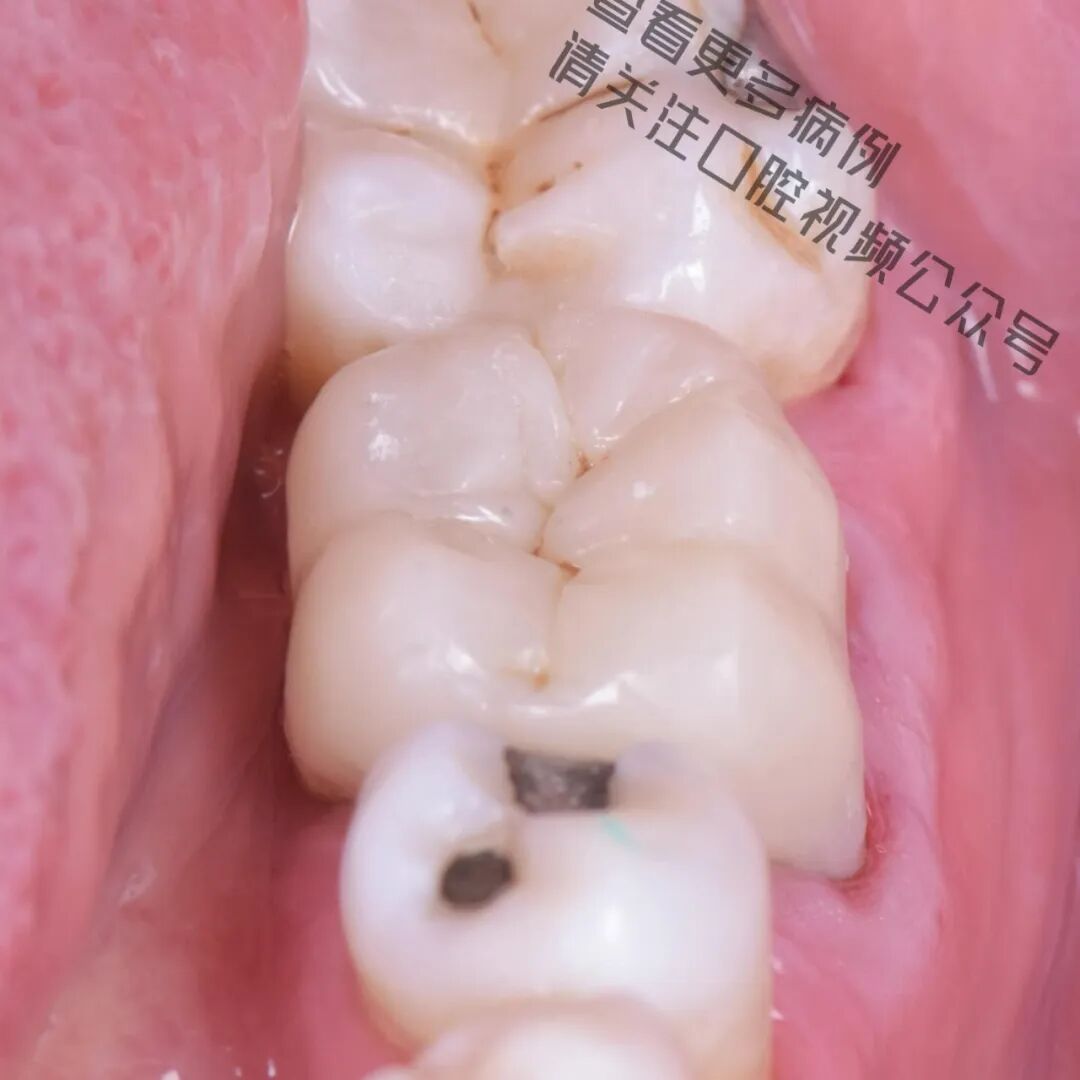

在这个病例中,仿生学理念(Biomimetics) 构成了整个治疗方案的核心基础。尽管牙齿结构已经严重脆弱化,但我们依然成功地恢复了其功能、强度与美观,完全遵循自然引导下的真正修复牙科原则。